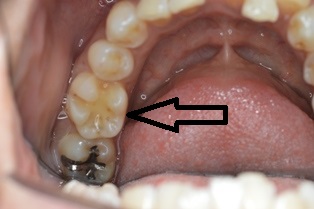

2016年4月26日 / 最終更新日時 : 2019年7月1日 まえだ歯科 ブログ ジルコニアインレー 術前 術後 下の奥歯にジルコニアインレーをセットしました。ジルコニアも材質が改良されてきて、いい色が出るようになってきました。 歯科医師 前田